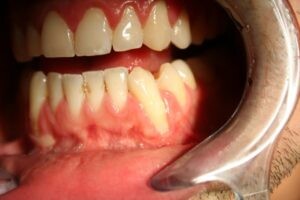

Receding gums are best avoided for several good reasons. Gum recession can lead to tooth sensitivity and even affect your smile, but that’s not all. Your gums (or gingiva) are critical in protecting the bone that holds your teeth in place. If the gums begin to shrink away, tooth roots can be exposed. Tooth roots can be more easily worn away than enamel covered surfaces and are susceptible to decay.

Exposed tooth roots that cause sensitivity

Shrunken gums